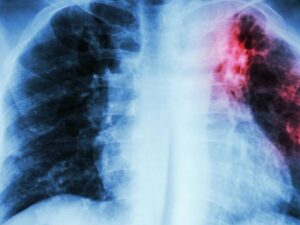

La Fibrosis Pulmonar no es una sola enfermedad, sino la consecuencia de más de 200 enfermedades pulmonares intersticiales. Se caracteriza por la inflamación de los pulmones y posterior cicatrización (fibrosis), condición que disminuye de manera gradual la capacidad respiratoria, provocando que los pacientes vivan con falta de aire constante.

La American Lung Association (ALA), define a la fibrosis pulmonary como una una enfermedad en la que hay cicatrices en los pulmones que dificultan la respiración:

“La fibrosis pulmonar es una forma de enfermedad pulmonar intersticial. Las enfermedades pulmonares intersticiales son un grupo de condiciones que causan inflamación y cicatrices alrededor de los pequeños sacos aéreos (alvéolos) en los pulmones”.

Por otro lado, hay muchos tipos diferentes de fibrosis pulmonar:

“El más común es la fibrosis pulmonar idiopática o FPI. Este tipo de fibrosis pulmonar no tiene causa conocida”.